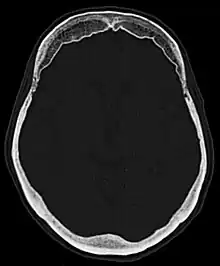

| Hyperostosis frontalis interna in a 74-year-old woman | |

Hyperostosis frontalis at CT